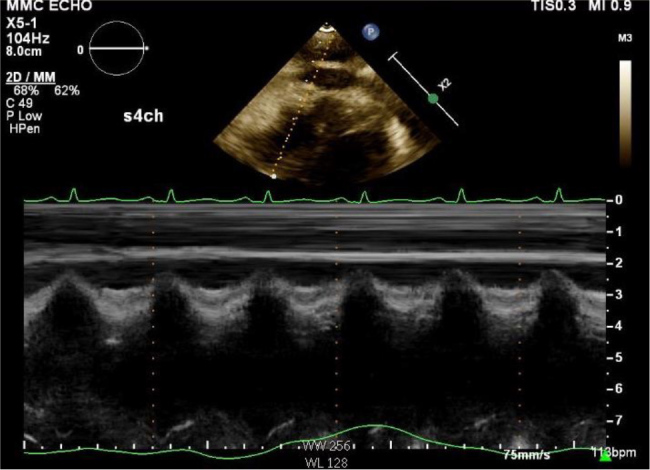

Case description: A 24-year-old female with cystic fibrosis, diagnosed at nine months, presented with two weeks of dyspnoea. Examination revealed bilateral rhonchi, facial oedema and non-pitting thigh oedema. Laboratory results showed a white blood cell count of 11.3 ×109/l, erythrocyte sedimentation rate of 99 mm/hr and C-reactive protein level of 45.3 mg/dl. Initially admitted for cystic fibrosis exacerbation, she was found to have pericardial effusion. Despite facial and lower extremity swelling, she denied cardiac symptoms. During hospitalisation, she developed haemodynamic instability requiring pericardiocentesis, with echocardiography confirming constrictive pericarditis. Chest computed tomography angiography showed pericardial calcifications; autoimmune workup was negative. She was discharged on colchicine with close follow-up.

Abstract Image